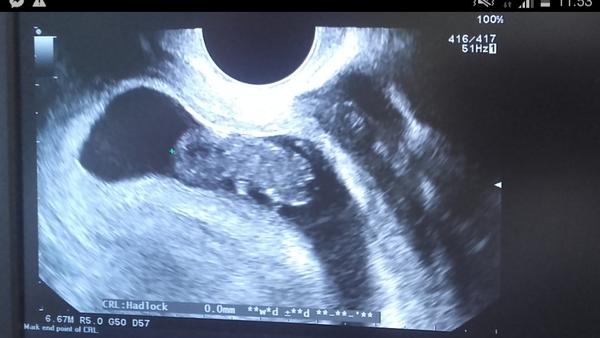

Dievčatá, prosím, poraďte mi. Dnes som bola na folikulometriu. Som 11DC. MS pravidelna vždy 26dni. Na usg mam na ľavom vajecniku folikul 17mm. To je vraj celkom ok vzhľadom na fázu cyklu. Či? Problém ale je, že na pravom vajecniku mam vodnatu cystu o veľkosti 6x2,7 cm. Vraj je to fest veľká cysta. Mate podobnu skúsenost? Môže ta cysta robiť problémy pri snažení sa? Som strasne vylakana.. Je možné aby som otehotnela keď by mi ten folikul co ma teraz 17mm narástol a praskol? Ci to nepôjde kvôli tej cyste na druhom vaječníku? Môj Dr bol neurčitý.. V piatok idem zase. Muž teraz sa bojím. Poradte mi pls.. Vdaka

@slniecko527 ahoj.. Tak dopadlo to zle :( na ľavom vajecniku je folikul 17mm,co je celkom ok vzhľadom na to ze som 11DC. Ale na pravom vajecniku mam veľmi veľkú cystu, 6x2,7cm :( je naplnená tekutinou, vraj môže sama puknut no nemusí. Som strašne vystrašená.. V piatok idem zas uvidím čo a ako.. :/